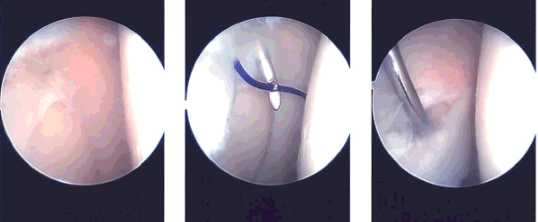

Intraoperative images

A lateral incision was given for the anterior portal for the arthroscope. The arthroscope was entered into the patellofemoral joint where synovitis was seen in the suprapatellar region.

There was Grade II to Grade III chondral damage on the posterior surface of the patella. The arthroscope was entered into the medial compartment where there was no meniscal tear. The cartilage was intact. There was synovitis in the medial compartment.

A medial anterior portal was made using the spinal needle. Examination of the anterior chondral notch showed an intact ACL. Examination of the lateral compartment showed a tear of the posterior horn of the lateral meniscus. There was synovitis in the lateral compartment also.

The shaver was used to do the synovectomy in the medial compartment as well as the lateral compartment. Shaving was done for doing meniscectomy of the posterior horn of the lateral meniscus. Up biter was also used for the meniscectomy.

Now the shaver and the arthroscope were entered into the patellofemoral compartment where extensive synovectomy of the synovium from the suprapatellar pouch as well as the medial and lateral gutter was performed. The chondral lesion of the posterior patella pouch was also debrided with the use of a shaver. After thorough irrigation pictures were taken and saved.